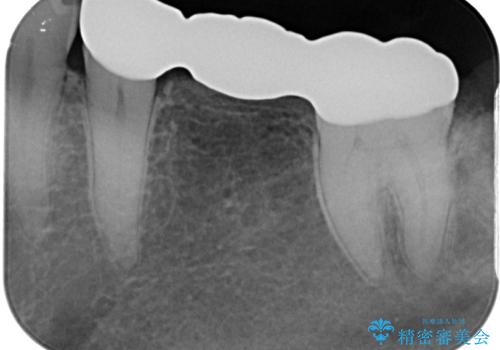

- 外れやすい銀歯をやり替えたいと来院された患者様です。

他院にて治療したインレーブリッジが何回か外れてつけ直しを繰り返しているため、外れないようにしてほしいとのことでした。

できるだけ外科処置は避けたいという患者様の希望と、すでにブリッジの土台となる両隣の歯を削って治療していることを考慮し、患者様と相談の上、今回はインプラントではなくフルジルコニアブリッジで治療することとしました。

より外れにくく精度の高いブリッジにするため、事前に親知らずの抜歯を当院で行いました。

外れる心配がなくなって安心して食事ができるとおっしゃっていました。